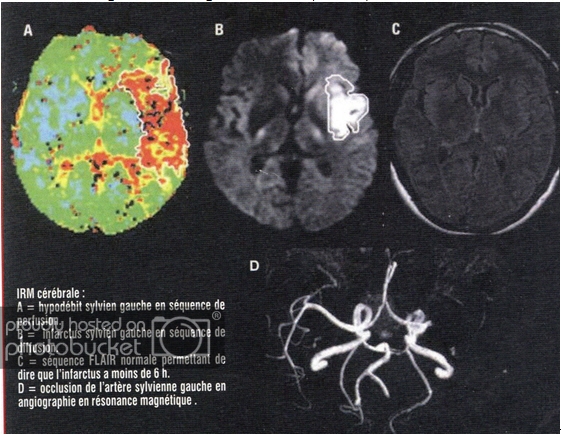

Default TAI BIẾN MẠCH MÁU NĂO

TAI BIẾN MẠCH MÁU NĂO

(TRANSIENT ISCHEMIC ATTACK AND

CEREBROVASCULAR ACCIDENT)

BS NGUYỄN VĂN THỊNH